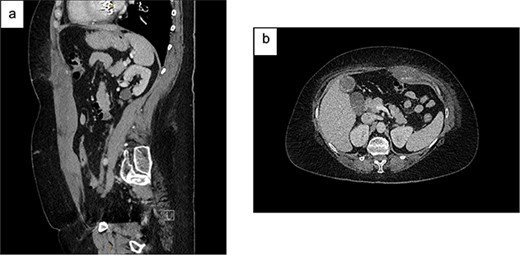

On examination, she was haemodynamically stable and afebrile. She had a soft abdomen, widespread abdominal bruising, and significant tenderness to the left of her umbilicus, without a discrete palpable mass. Urinalysis showed a trace of leucocytes but no blood or nitrites. Her blood tests showed haemoglobin 94 g/L, international normalised ratio 1.9, creatinine 63 μmol/L and estimated glomerular filtration rate (eGFR) >90 mL/min/1.73m2. A CT abdomen showed a left-sided RSH (62x38x131mm), with high-attenuating foci superiorly and inferiorly (Fig. 1). She was admitted to the Acute Surgical Unit and warfarin was withheld but therapeutic enoxaparin was continued on the advice of the Haematology team.

Contrast CT abdomen and pelvis (portal venous phase) demonstrating a left-sided RSH with active extravasation: (a) Sagittal view; (b) Axial view.